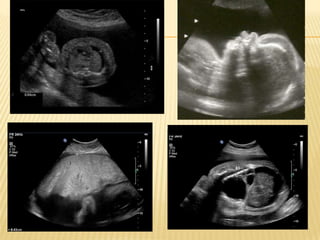

NIHF is established by the ultrasound

DEFINITION....... NIHF is establishedby the ultrasound findings of at least two of the following  Ascites  Pleural effusion: ANY fluid abnormal  Pericardial effusion: > than 2mm  Skin edema: > than 5mm on chest and scalp  Polyhydramnios: Max pocket > 8cm, or AFI > 24cm